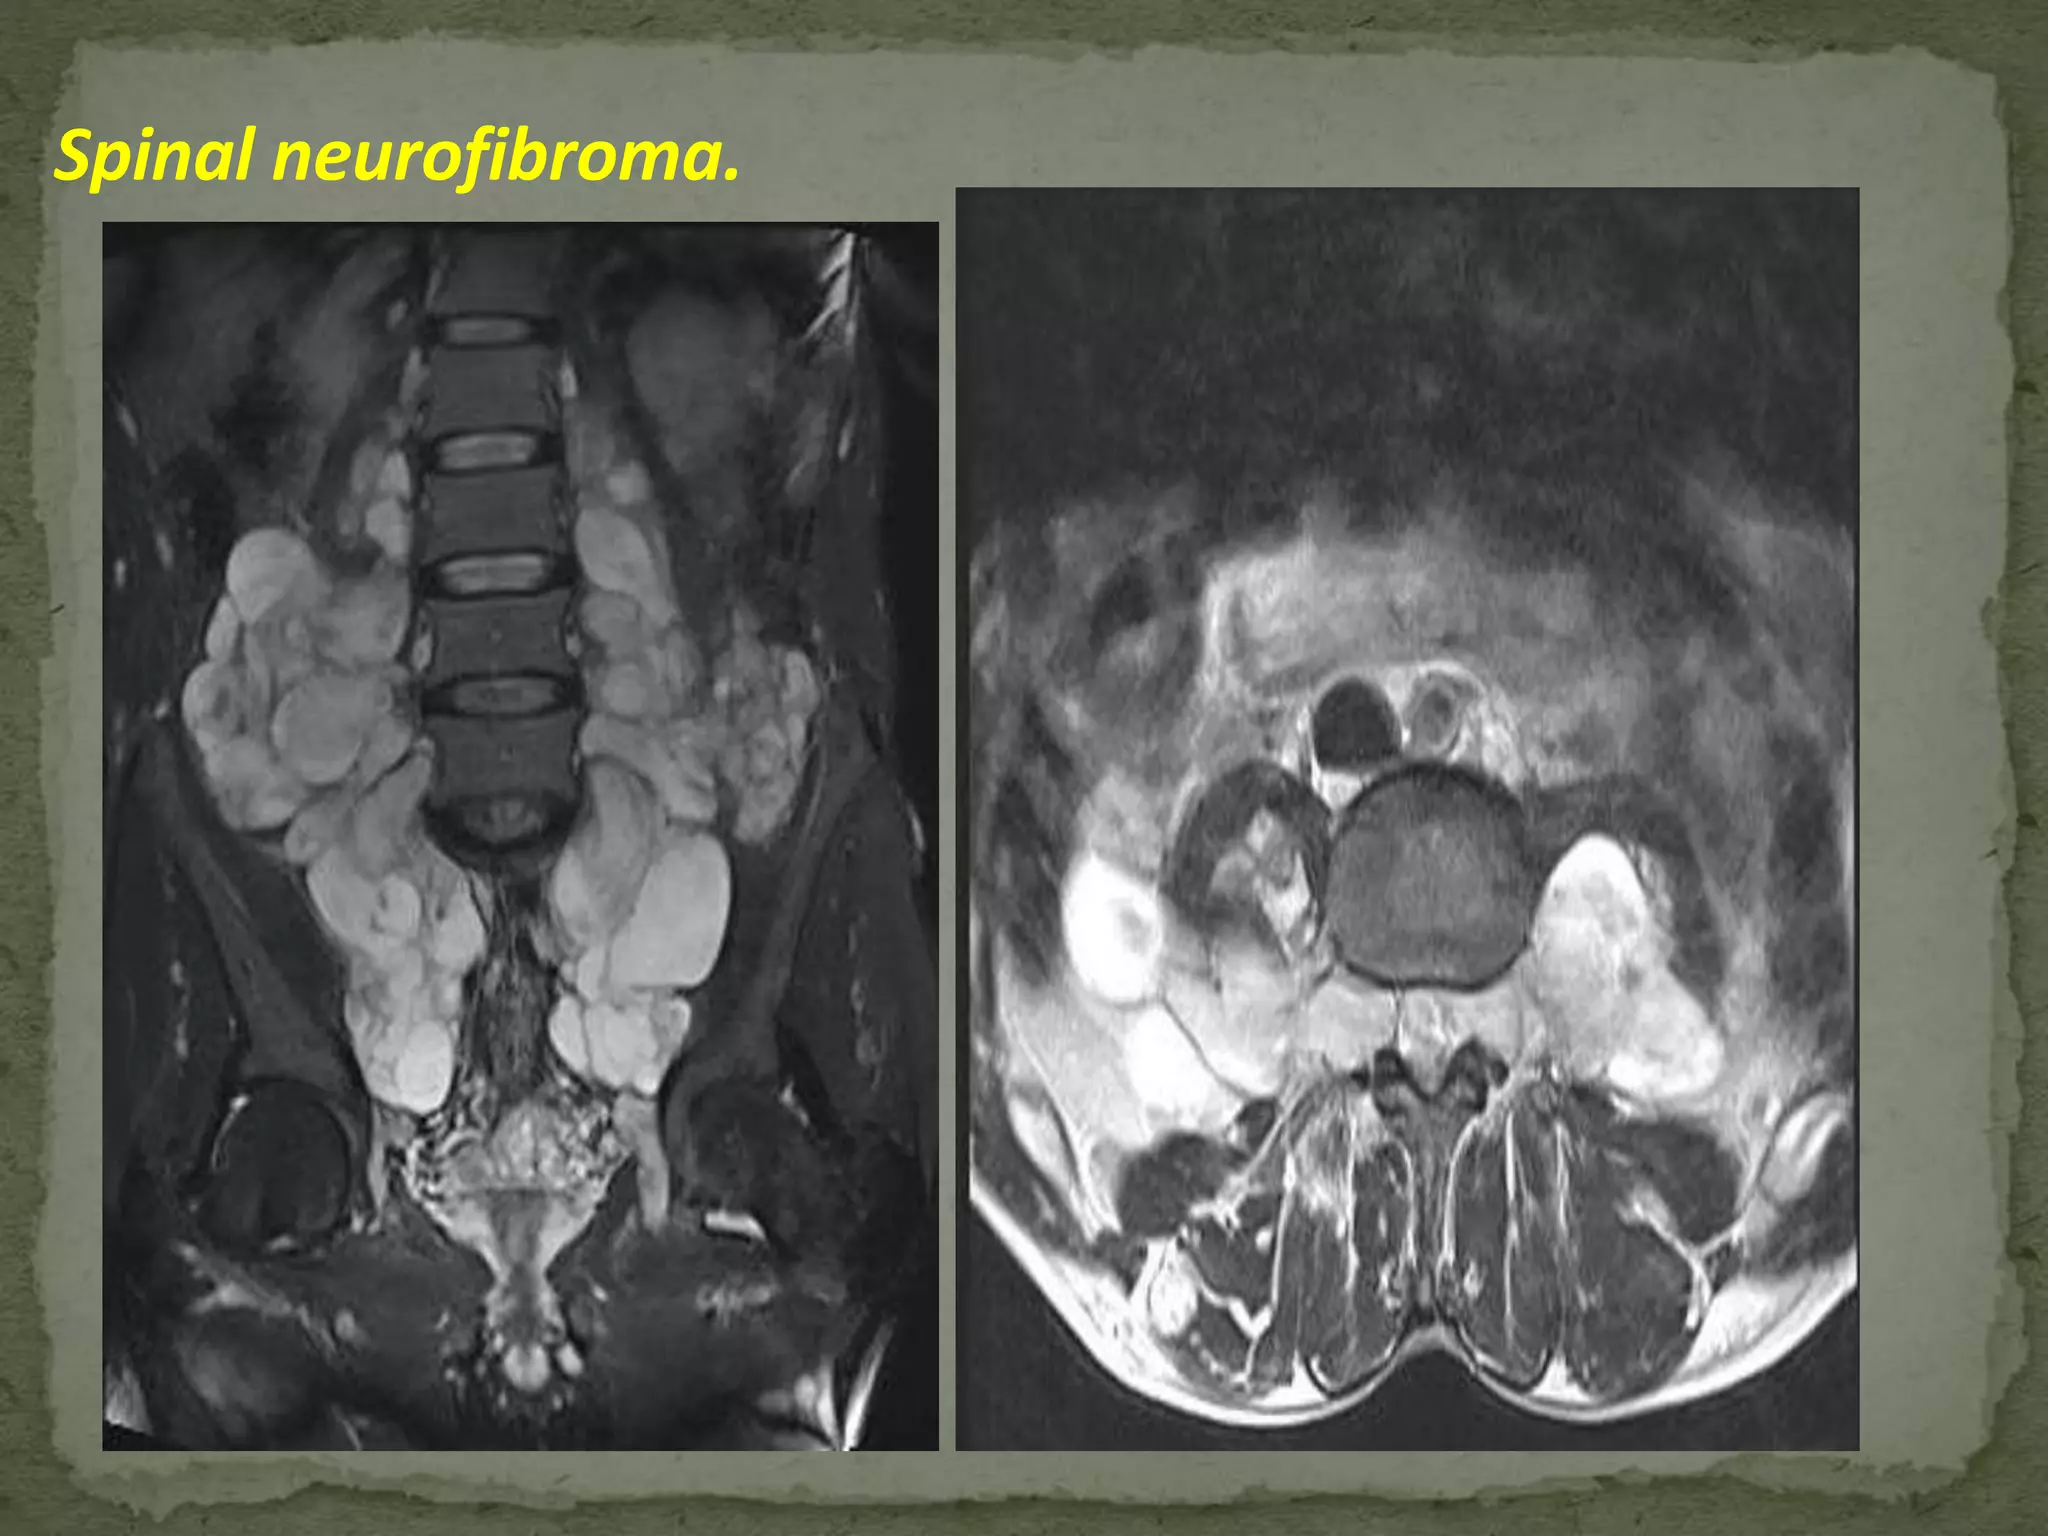

 Schwannomas and Neurofibromas.

 Schwannomas are most common

 Neurofibromas generally occur in association with

neurofibromatosis

 Approximately 50% of nerve sheath tumors are

intradural-extradural (dumbbell- shaped) in location

and 50% are purely extradural.

Spinal neurofibroma.